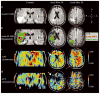

Chemical exchange saturation transfer (CEST)-derived, pH-weighted, amide proton transfer (APT) MRI has shown promise in animal studies for the prediction of infarction risk in ischemic tissue. Here, APT MRI was translated to patients with acute stroke (1-24 h post-symptom onset), and assessments of APT contrast, perfusion, diffusion, disability and final infarct volume (23-92 days post-stroke) are reported. Healthy volunteers (n = 5) and patients (n = 10) with acute onset of symptoms (0-4 h, n = 7; uncertain onset <24 h, n = 3) were scanned with diffusion- and perfusion-weighted MRI, fluid-attenuated inversion recovery (FLAIR) and CEST. Traditional asymmetry and a Lorentzian-based APT index were calculated in the infarct core, at-risk tissue (time-to-peak, TTP; lengthening) and final infarct volume. On average (mean ± standard deviation), control white matter APT values (asymmetry, 0.019 ± 0.005; Lorentzian, 0.045 ± 0.006) were not significantly different (p > 0.05) from APT values in normal-appearing white matter (NAWM) of patients (asymmetry, 0.022 ± 0.003; Lorentzian, 0.048 ± 0.003); however, ischemic regions in patients showed reduced (p = 0.03) APT effects compared with NAWM. Representative cases are presented, whereby the APT contrast is compared quantitatively with contrast from other imaging modalities. The findings vary between patients; in some patients, a trend for a reduction in the APT signal in the final infarct region compared with at-risk tissue was observed, consistent with tissue acidosis. However, in other patients, no relationship was observed in the infarct core and final infarct volume. Larger clinical studies, in combination with focused efforts on sequence development at clinically available field strengths (e.g. 3.0 T), are necessary to fully understand the potential of APT imaging for guiding the hyperacute management of patients.